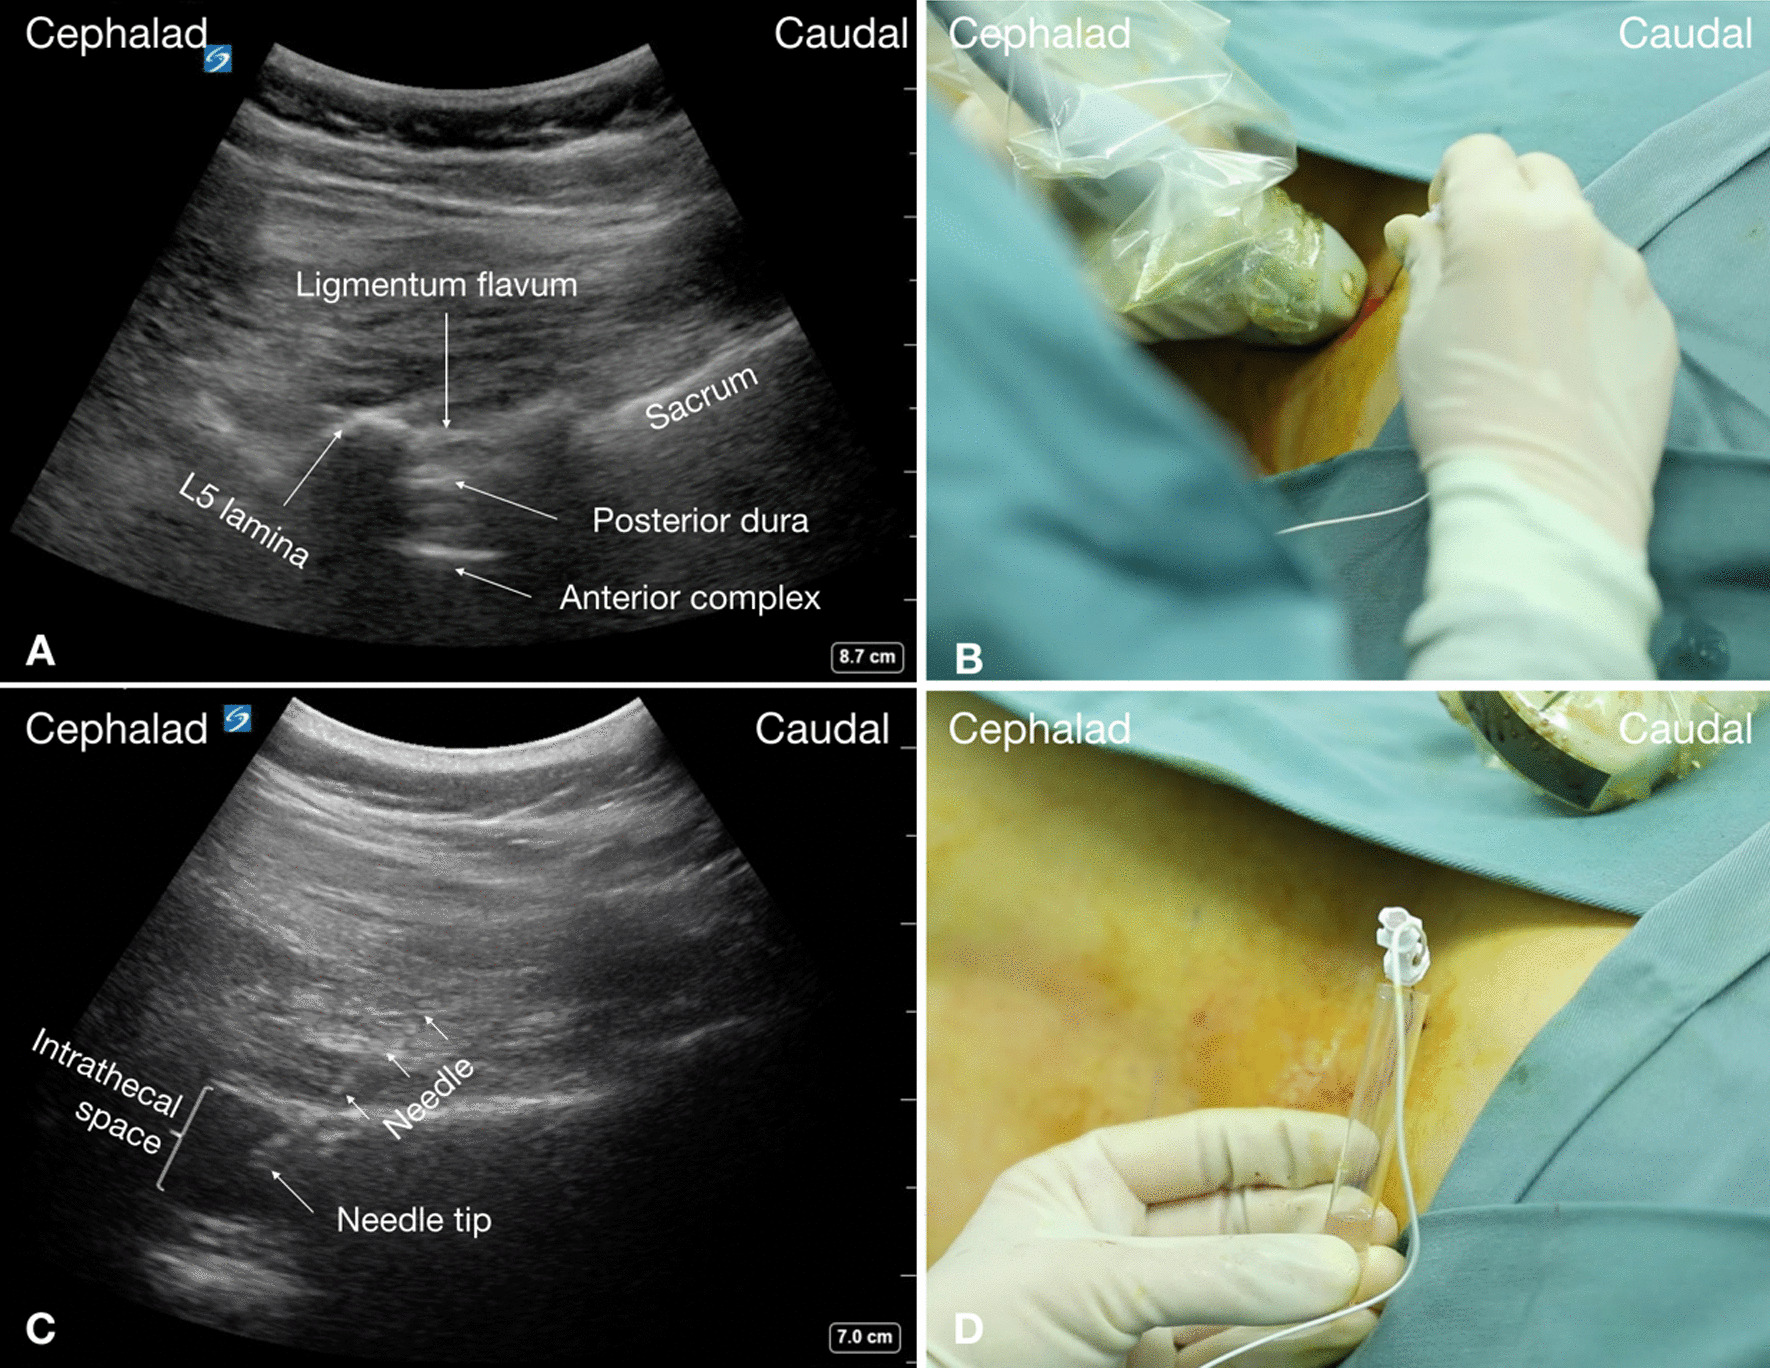

Fig. 2.

Real-time ultrasound-guided lumbar puncture in a SMA patient with severe scoliosis. A Paramedian sagittal oblique interlaminar sonogram of the lower lumbar spine (L5–S1) with the neuraxial structures clearly visualized through the acoustic window of the interlaminar space. B Ultrasound probe position of paramedian sagittal oblique scan at the level of lamina and needle orientation for lumbar puncture with in-plane approach. C Sonogram obtained when needle inserted into the intrathecal space. D Free flow of clear CSF is noted from the puncture needle

During lumbar spinal sonography, the paramedian sagittal oblique interlaminar approach possesses the advantage of providing a better sonographic window into the vertebral canal from the interlaminar space compared with the interspinous space (median) approach [18, 19], and is more successful in patients with a difficult anatomy [20, 21]. Performers of the technique should be familiar with the sonoanatomy of the interlaminar, the intrathecal, and the surrounding bony structures. Sonographically, the interlaminar space is the gap between the adjoining lamina and is the “acoustic window” through which the neuraxial structures are visualized within the spinal canal (Fig. 2A). The ligamentum flavum appears as a hyperechoic band across adjacent lamina (Fig. 2A). The posterior dura is the next hyperechoic structure anterior to the ligamentum flavum (Fig. 2A), and the epidural space between the ligamentum flavum and the posterior dura is hypoechoic. The ligamentum flavum and the posterior dura may also be seen as a single linear hyperechoic structure, which is referred to as the “posterior complex”. The intrathecal space with the CSF is the anechoic space anterior to the posterior dura. The deeper linear hyperechoic structure is the “anterior complex” composed of the anterior dura, the posterior longitudinal ligament, and the posterior surface of the vertebral body, which are of similar echogenicity and closely opposed to each other. To accurately obtain this paramedian sagittal oblique interlaminar window in SMA patients with complex deformity of the spine, we recommend to strictly follow the currently used three-step scan protocol [10].